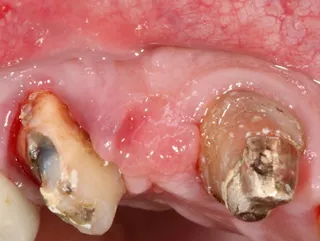

Initial situation

1. The two mesially tipped upper canines and first premolars supported two bridges that had been remade 3 times. Repeated decementation in the upper left quadrant and an infection in 2018 made the patient decide to agree to the proposed implant treatment.